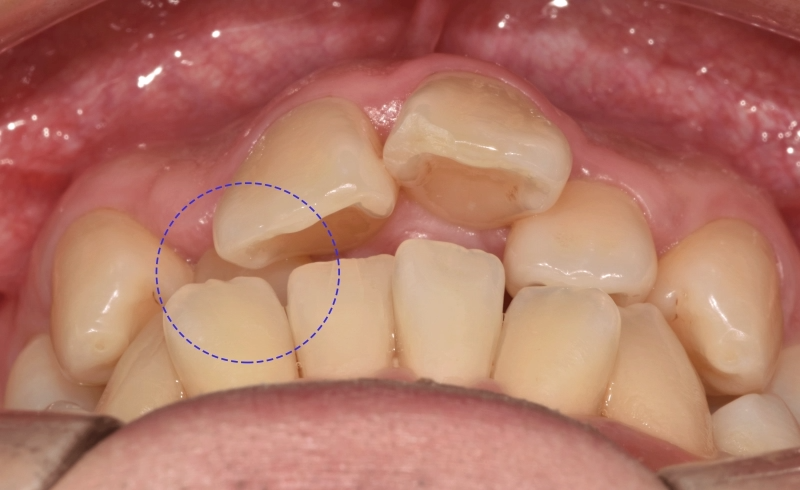

특히나 전치부에 집중된 총생(crowding)은

배열을 들쑥날쑥하게 만듭니다.

사진에서 보여지듯이 12번은

반대교합의 형태도 나타내고 있었는데요.

다른 곳들은 윗니가 아랫니를 덮는 반면에

오른쪽 아랫니 송곳니 부분이 위쪽의 12번을

덮고 있는 형태로 반대교합을 보여줍니다.

이러한 총생은 이가 올바르게 자리 잡지 못하고

겹치거나 삐뚤어지게 나온 상태를 말합니다.

오래 방치할수록 턱뼈의 크기와 치아 크기의 불균형을

만드는 원인이 됩니다.

이렇게 좁은 공간 안에서

이들이 비정상적으로 배열되는 것이 특징이며,

주로 전치부에 자주 나타납니다.

맹출 할 공간의 부족으로 인해 총생이 생겨나면서

이로 인해 앞니 뻐드렁니도 자연스럽게

만들어져 돌출된 느낌을 줍니다.